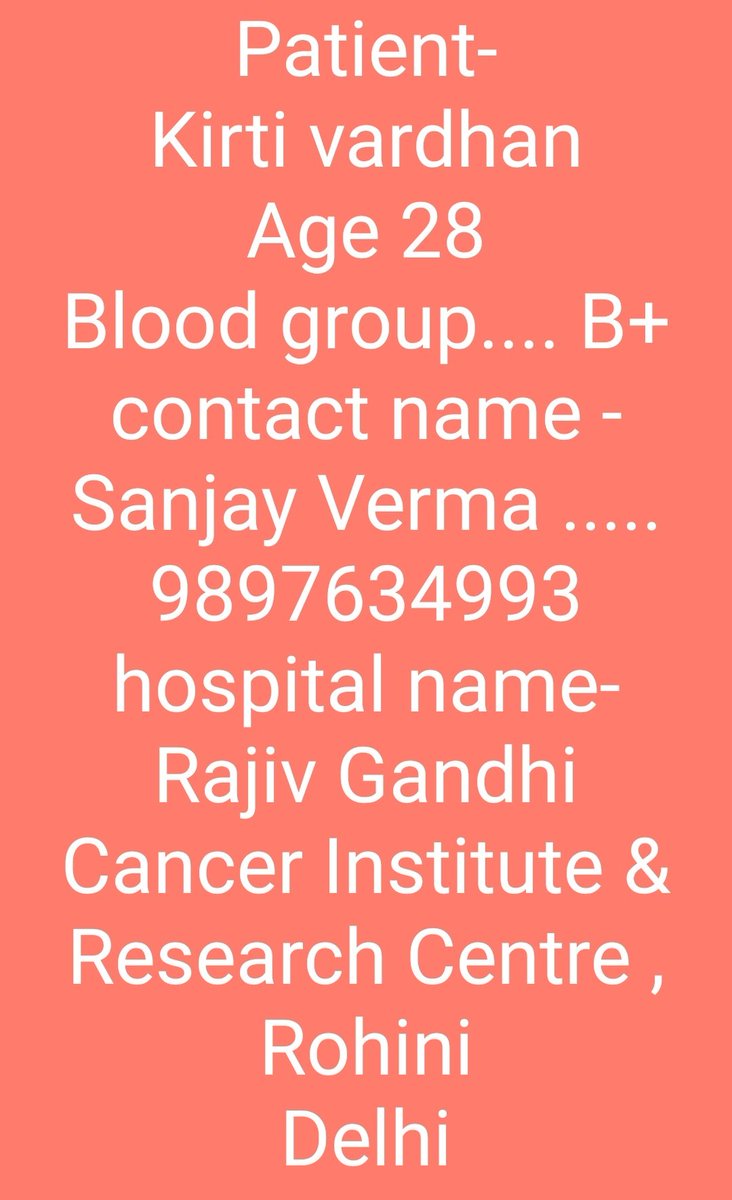

Hello everyone, Need urgent help. Family frnd is diagnosed with huge blood deficiency & requires all ur wishes & help. Sharing contact details - Blood group- B+ contact - Sanjay Verma, No.- 9897634993 Hospital - Rajiv Gandhi Cancer Inst., Rohini, Delhi @BloodDonorsIn